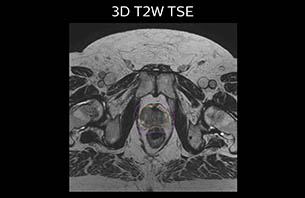

MR-only based planning for prostate cancer radiation therapy treatment

A 77-year-old male with prostate cancer cT3aN0M0, Gleason 8 and PSA 52 μg/L referred to androgen deprivation and radiation therapy with a prescribed dose of 50 Gy to the pelvic lymph node regions and 76 Gy to the prostate.

Turku MRI-T2W therapy case 2

The 3D T1W FFE mDIXON sequence provides in-phase, water and fat images in one acquisition. Target and organs-at-risk are delineated on the 3D T2W TSE images. Prostate GTV is shown in orange, PTV in purple. The 3D bFFE sequence is used by the planner to mark the position of the fiducial markers (gold anchors) and contours are transferred to the digitally reconstructed radiographs (DRRs).